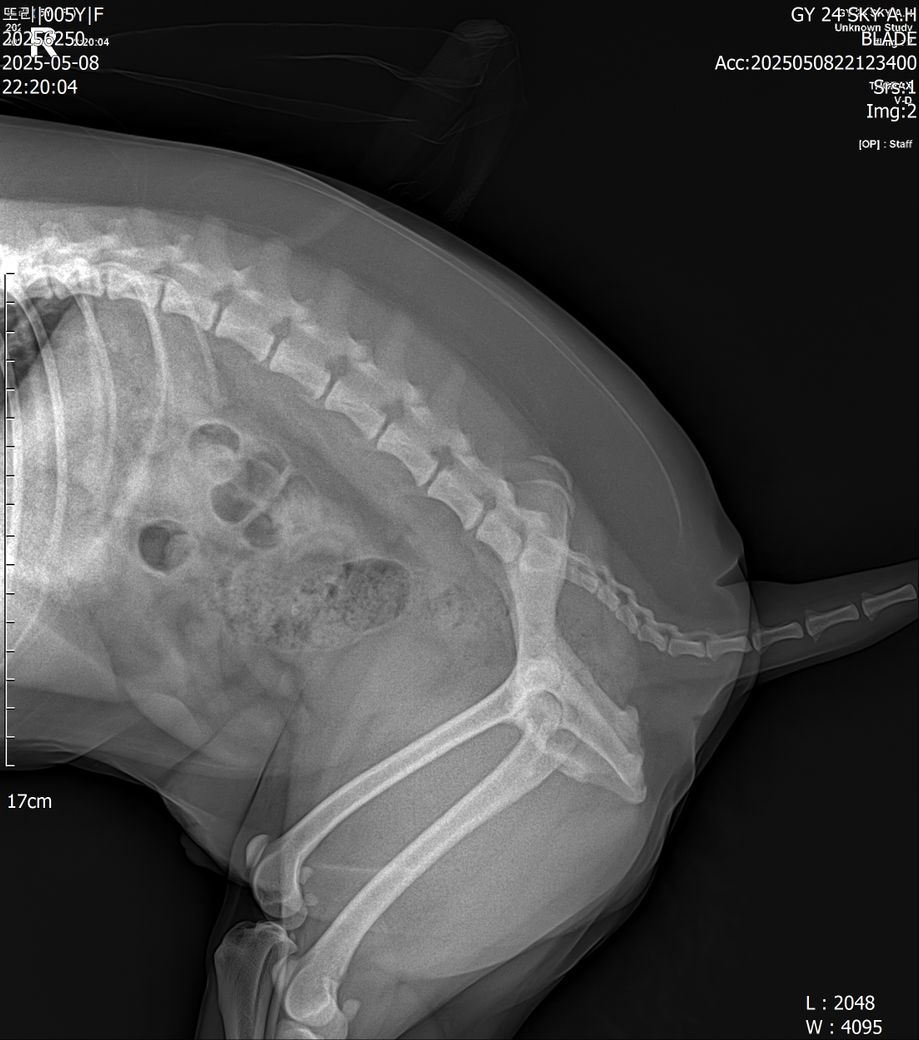

엑스레이는 피 나온날 찍은 사진 입니다